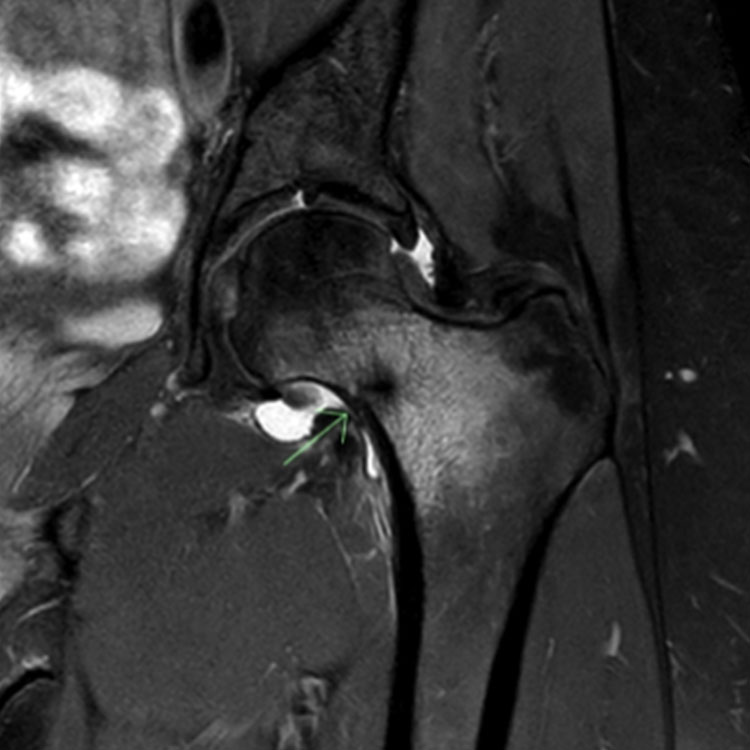

MRI

Η μαγνητική τομογραφία παρέχει το πλεονέκτημα της πολυεπίπεδης απεικόνισης της αξονικής τομογραφίας με την ανίχνευση της οστικής παθοφυσιολογίας της οστικής τομογραφίας αλλά χωρίς την ακτινοβολία. Ένα κάταγμα από στρες μπορεί να αναγνωριστεί ως οίδημα περιοστικού ή μυελού των οστών στην μαγνητική τομογραφία καθώς και οπτικοποίηση μιας γραμμής κατάγματος σε ορισμένες αλληλουχίες. Ομοίως με τη σάρωση οστών, το οίδημα του μυελού των οστών δεν είναι ειδικό για κάταγμα στρες στην μαγνητική τομογραφία και το οίδημα μπορεί να παραμείνει για κάποιο χρονικό διάστημα μετά την επίλυση του κατάγματος στρες.

ΕΣΩ ΣΦΥΡΟ

Τα κατάγματα του έσω σφυρού από πίεση είναι σχετικά ασυνήθιστα (0,6-4,1% όλων των καταγμάτων λόγω στρες), αλλά μπορεί να προκαλέσουν σημαντική νοσηρότητα και απώλεια χρόνου παιχνιδιού.26 Αυτά τα κατάγματα συμβαίνουν σε δρομείς και αθλήματα τρεξίματος και είναι πιο συχνά σε σκελετικά ώριμους αθλητές.

Διερευνήσεις

Τα κατάγματα του έσω σφυρού του στρες γενικά δεν είναι ορατά στις ακτινογραφίες. Η γραμμή του κατάγματος συνήθως εκτείνεται κατακόρυφα από την κνημιαία πλάκα, αν και μπορεί να διατρέχει λοξά τον έσω σφυρό και μπορεί να εκτείνεται στην εξωτερική φλοιώδη επιφάνεια.27

Οι σαρώσεις μαγνητικής τομογραφίας έχουν υψηλή ευαισθησία και υψηλή ειδικότητα για το στρες των οστών.28,29 Μπορεί να χρειαστούν αξονικές τομογραφίες για την περαιτέρω αξιολόγηση της πλήρους έκτασης της γραμμής του κατάγματος και την αξιολόγηση του φλοιώδους οστού.

Εικόνες για να δείτε παραδείγματα καταγμάτων πίεσης έσω σφυρού.